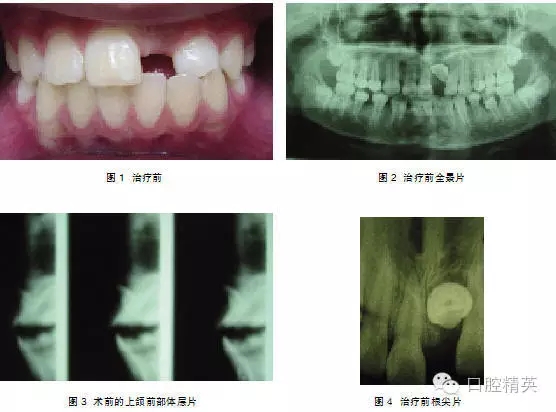

典型病例2:患者,女,10歲,因1|未萌來我院就診(圖1)。

檢查:1|未萌, |1全萌, 2|1之間間隙為5mm。X線示:1| 骨內埋伏,倒置,牙冠的舌側向外,彎根。 |1牙根已形成。(圖2、3)。

處理:2004年3月行外科開窗+正畸牽引治療,7個月后檢查:1|已萌出,未完全到位,1|唇側牙根處稍隆起,即為彎曲的牙根。因1|為彎根比較嚴重,如完全排齊有可能使牙根暴露,故未完全排齊(圖4、5)。